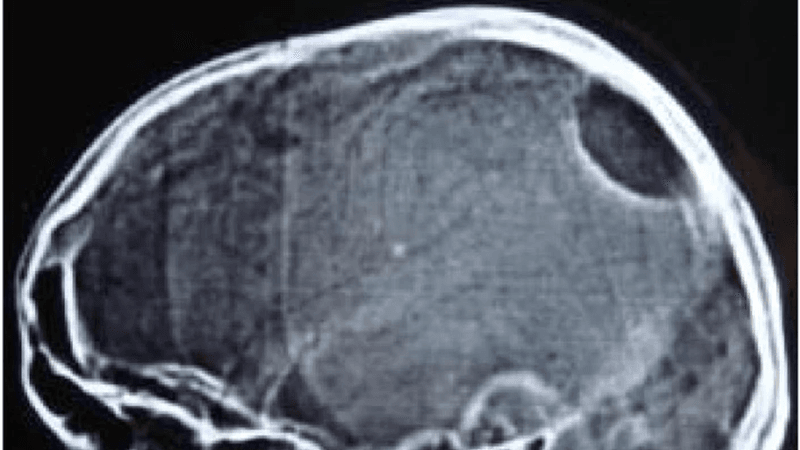

TBIs are very common in contact sports such as American football, rugby, and soccer, where players hit the ball with their heads, as well as other physical contact sport like wrestling or mixed martial arts. However, quickly evaluating if someone has experienced a TBI has been challenging. Patients usually end up going to hospital a fair period of time after experiencing the injury, as there is no current immediate evaluation test available. The diagnosis of a TBI currently requires a person to go to hospital for a CT scan after they experience symptoms of a concussion, and then receive the scan to rule on whether they have a TBI.

Now the Abbott handheld device is set to change that, allowing for rapid testing after a suspected concussion that could deliver the results within 15 minutes. A negative test using the handheld device could rule out the requirement of getting a CT scan to test for a TBI, a positive result would mean they should get a CT scan to confirm if it is a TBI and how severe it is so that they can get the clinical care they need.

TBIs are generally concerning. Research has shown that repeated head injuries or concussions could lead to major mental impairment, as well as increasing the chances of developing dementia, hence more needs to be done to tackle clinical care and diagnosing patients with TBI faster.